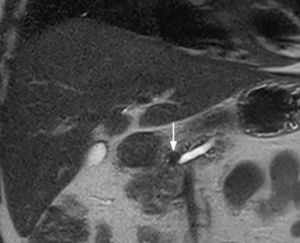

Aspetti RM: minuto nodulo della testa pancreatica ipointenso in T1.